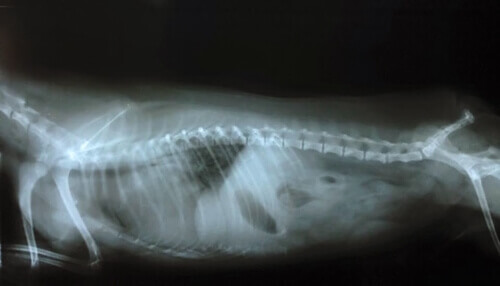

La diagnosi differenziale per la sindrome di Wobbler si ottiene osservando la colonna vertebrale e le rispettive vertebre. Per fare questo, il veterinario richiederà l’esecuzione di un test a raggi X, una tomografia computerizzata, una risonanza magnetica e un mielogramma.